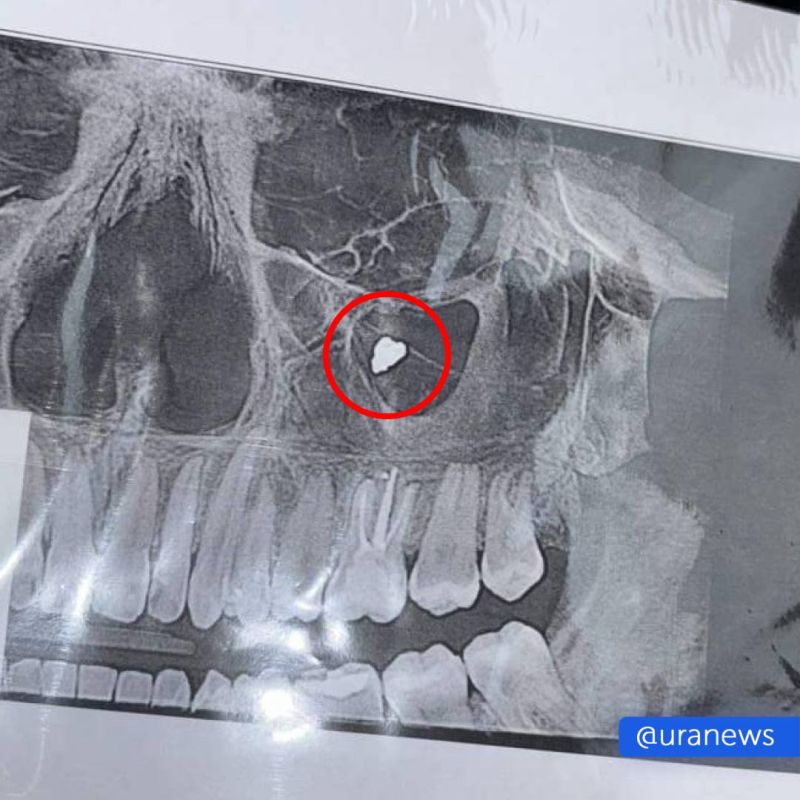

Инцидент произошел во время сложного лечения зуба, когда врач перепломбировал каналы.Как рассказала Полина URA.RU, все эти годы ее периодически беспокоили боли, которые она принимала за зубные. Проблема обнаружилась, когда после переохлаждения у...